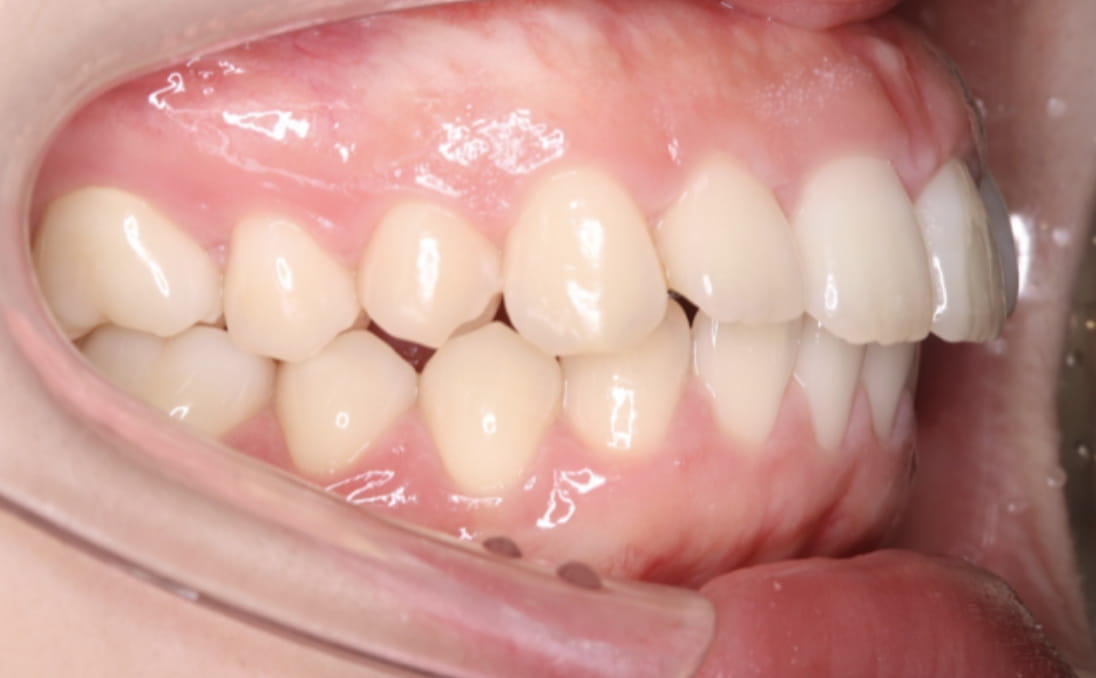

《上下顎前突》

症例

主訴 口ゴボが気になる

治療装置 ハーフリンガル矯正(上顎裏側・下顎表側)

抜歯 抜歯あり

診断名 上下顎前突(口ゴボ)

副作用 歯肉退縮・歯根吸収・歯髄・壊死・癒着による予期せぬ歯の動き

上下顎ともに裏側で装置を完全に隠しながら、アンカースクリューで前歯をしっかり後退。見た目と仕上がりを両立した症例。

治療前

治療中①